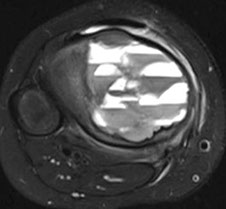

Aneurysmal bone cyst (ABC)

- usually an impressive, "benign" expansile lesion that destroys bone; etiology unknown, prolly a rxn to interosseous hemorrhage

- seen in pts <20 yo, presenting c pain, swelling, MC in metaphysis

-- can compress nerve root if goes vertebral and grow very fast

Imaging: MC in metaphysis of long bones or posterior aspect of vertebra, "soap bubble" characteristic

- CT shows thin rim of sclerosis at margins, and can have fluid-fluid levels (double meniscus 2/2 old blood c lighter overlying watery fluid, or can have soap-bublle appearance

Micro: if intact, see cavernous blood-filled spaces lined by fibrous septae

- septae made of loose / edematous tissue c spindle cells, giant cells, capillaries and thin strands of osteoid or bone + mixed inflam

- can have lots o mits, but not that much atypia